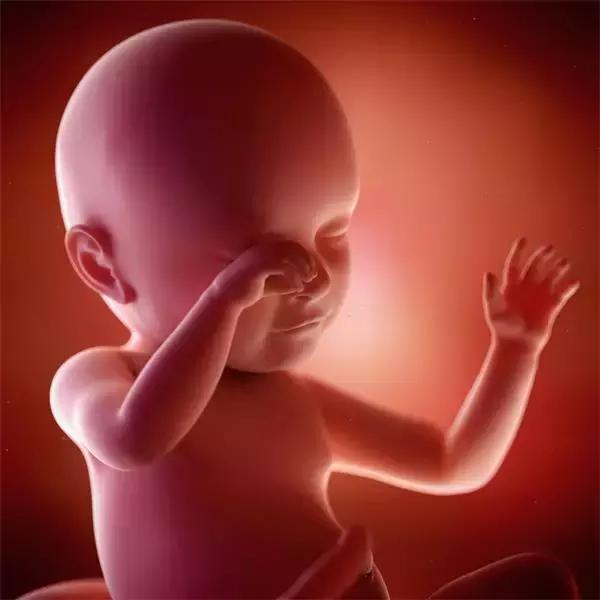

四维彩超可立体显示胎儿的颜面部、各器官的发育情况以及胎儿的年龄、大小等,甚至胎儿在母体里的状态,动作也可以观察到;对胎儿畸形,如唇裂、腭裂、脊柱裂、骨骼发育异常、心脏、大脑畸形等能早期诊断。

四维和三维原理一样,三维是静态的,四维是动态的结果,关键是对羊水多少的判断和处理,三维和四维都是一种比较准确的排除胎儿的外观的畸形的检查手段,三维只能拍摄到宝宝的照片,四维可以录制宝宝视频的。 三维彩超侧重观察五脏六腑是否畸形,排除结构畸形。四维彩超还观察运动神经系统是否正常,运动是否协调。